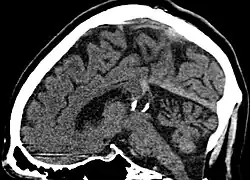

Calcified cyst of pineal gland in CT. Sagittal MPR.